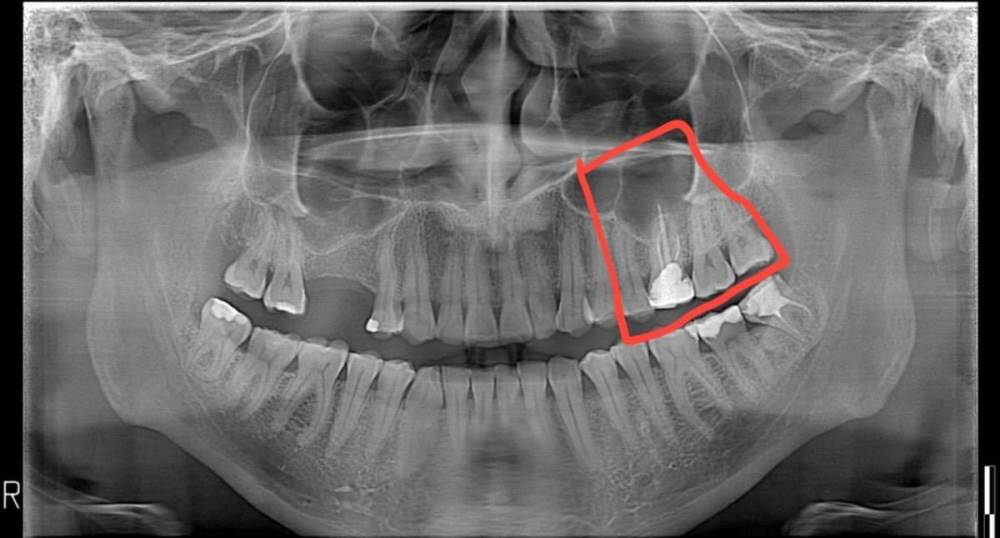

randomsctions Опубликовано 24 апреля, 2023 Автор Поделиться Опубликовано 24 апреля, 2023 Добрый день! Наконец-то уговорил врачей сделать КТ. При постукивании, если внимательно прислушиваться, выделяется нижний зуб (обвел красным), ну и верхний депульпированный. Дантист быстро показала КТ эндодонтисту, оба врача ничего страшного там не увидели. Боль продолжается, в состоянии покоя снижается до 1-2, после еды или воды возрастает до 7-8, потом плавно возвращается к 1-2. 741021604_AndreiTiupovCBTCscan.dcm Ссылка на комментарий

Carioznik Опубликовано 25 апреля, 2023 Поделиться Опубликовано 25 апреля, 2023 (изменено) 22.04.2023 в 18:08, randomsctions сказал: Удалили нерв и запломбировали канал сейчас там временная пломба? Судя по КТ - каналы не до конца сделаны. (от этого могут сохраняться боли) На зубе 26 (верхний с большой пломбой) - приличный очаг воспаления из-за пропущенного, когда-то при лечении зуба, канала. Каналы в нём перелечить можно , но есть вопрос с восстановлением и дальнейшим прогнозом (от зуба скорее всего ничего не останется и восстановить его уже не получится нормально , соответственно есть вероятность удаления зуба) 18 часов назад, randomsctions сказал: При постукивании, если внимательно прислушиваться, выделяется нижний зуб Возможно есть рецидив кариеса под пломбой , но это только предположение, нужен очный осмотр. (вряд-ли он причина ваших проблем, но я бы взял его на заметку) еще бы верхний предпоследний более детально посмотреть (очно и доп.прицельный снимок) пока вывод такой: долечить зуб , где удалили нерв. Далее переходить к верхнему зубу с большой пломбой. PS сделайте хоть фотографию во рту, если получится. может что-то еще прояснится Изменено 25 апреля, 2023 пользователем Carioznik 1 Ссылка на комментарий